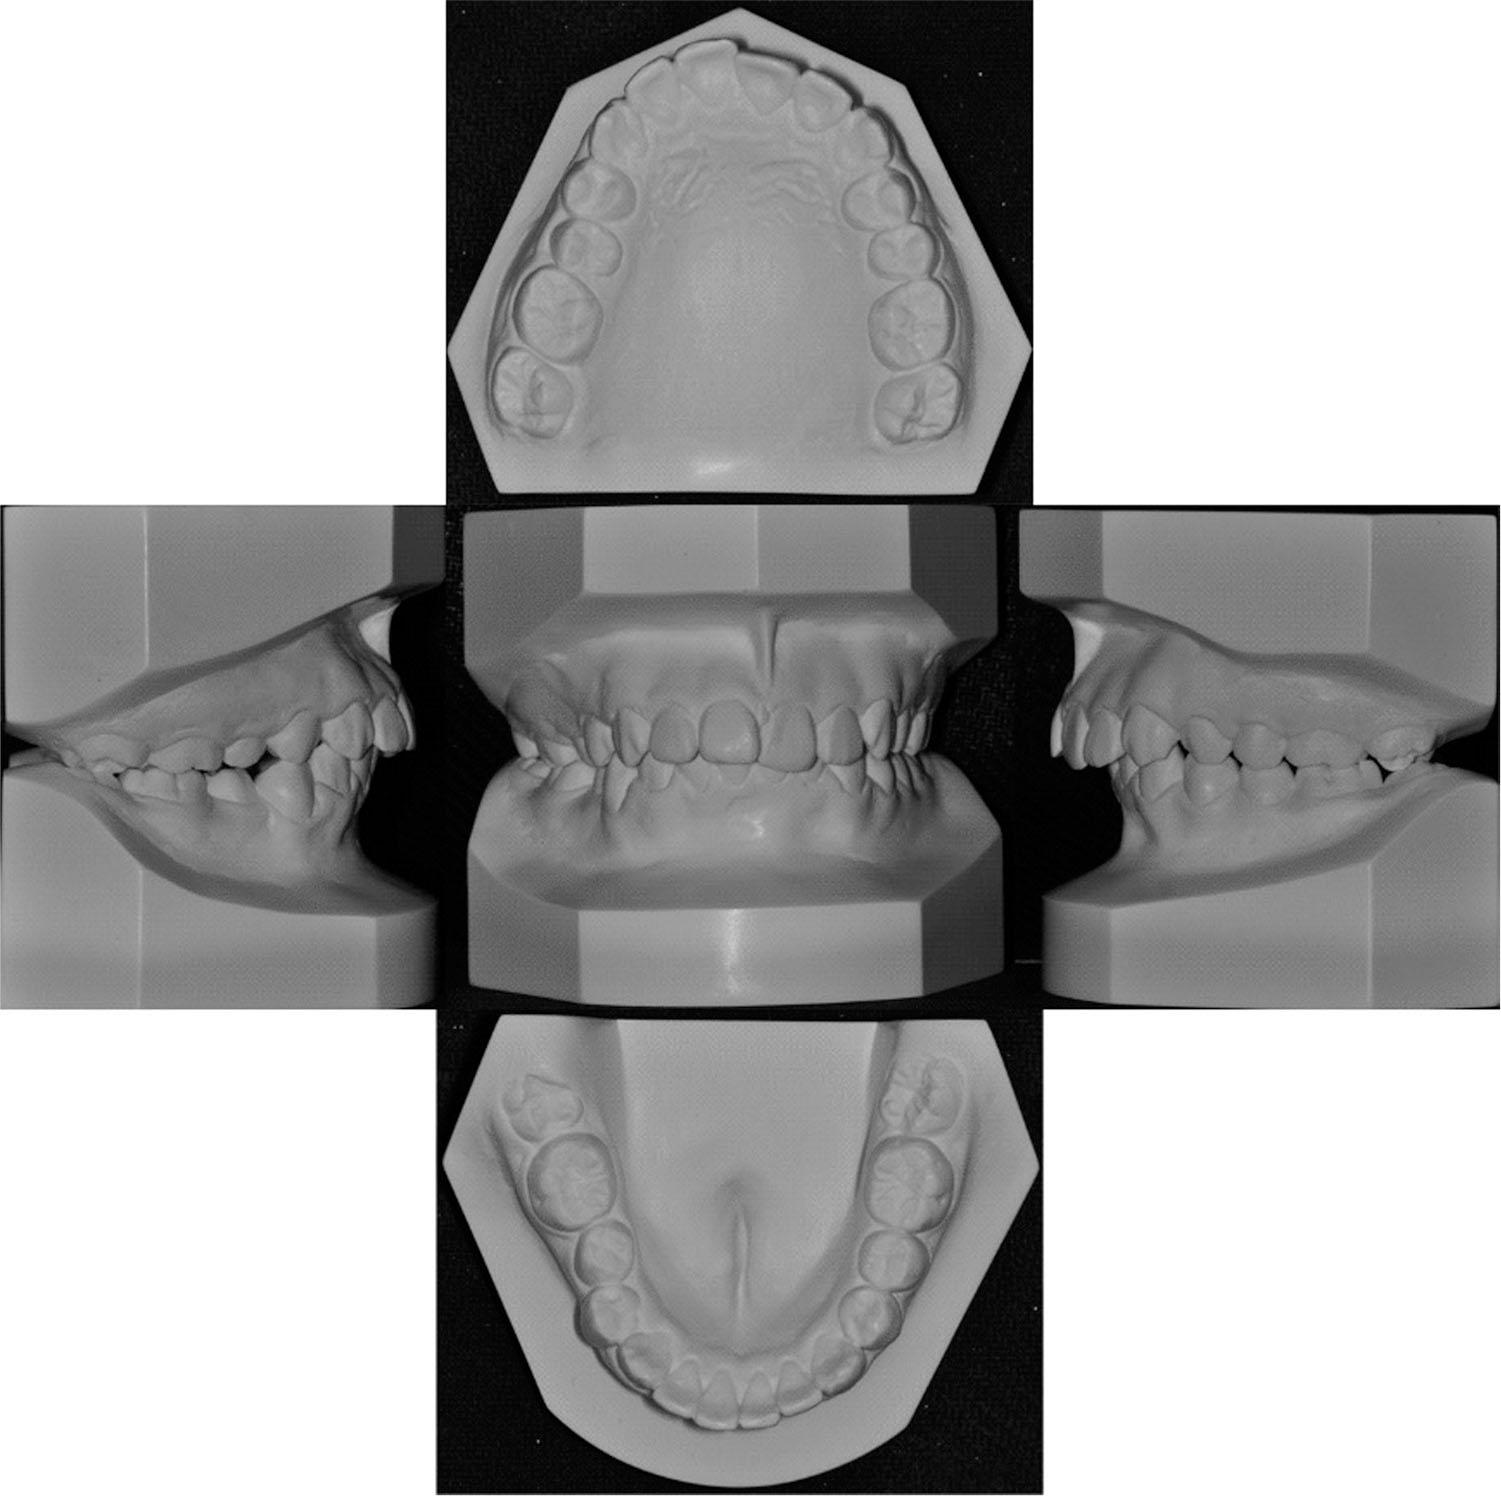

Figure 1.

Figure 2.